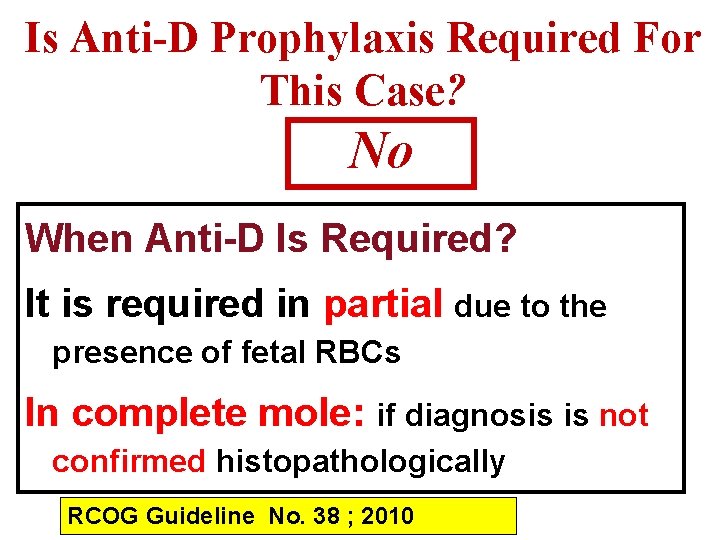

Is Anti-D Prophylaxis Required For This Case? No When Anti-D Is Required? It is required in partial due to the presence of fetal RBCs In complete mole: if diagnosis is not confirmed histopathologically RCOG Guideline No. 38 ; 2010